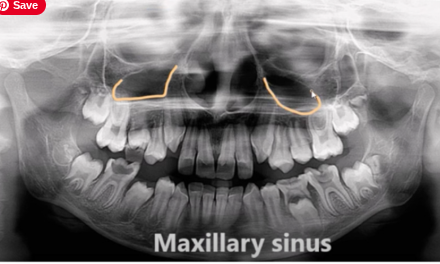

Maxillary sinus

dark area above upper molars